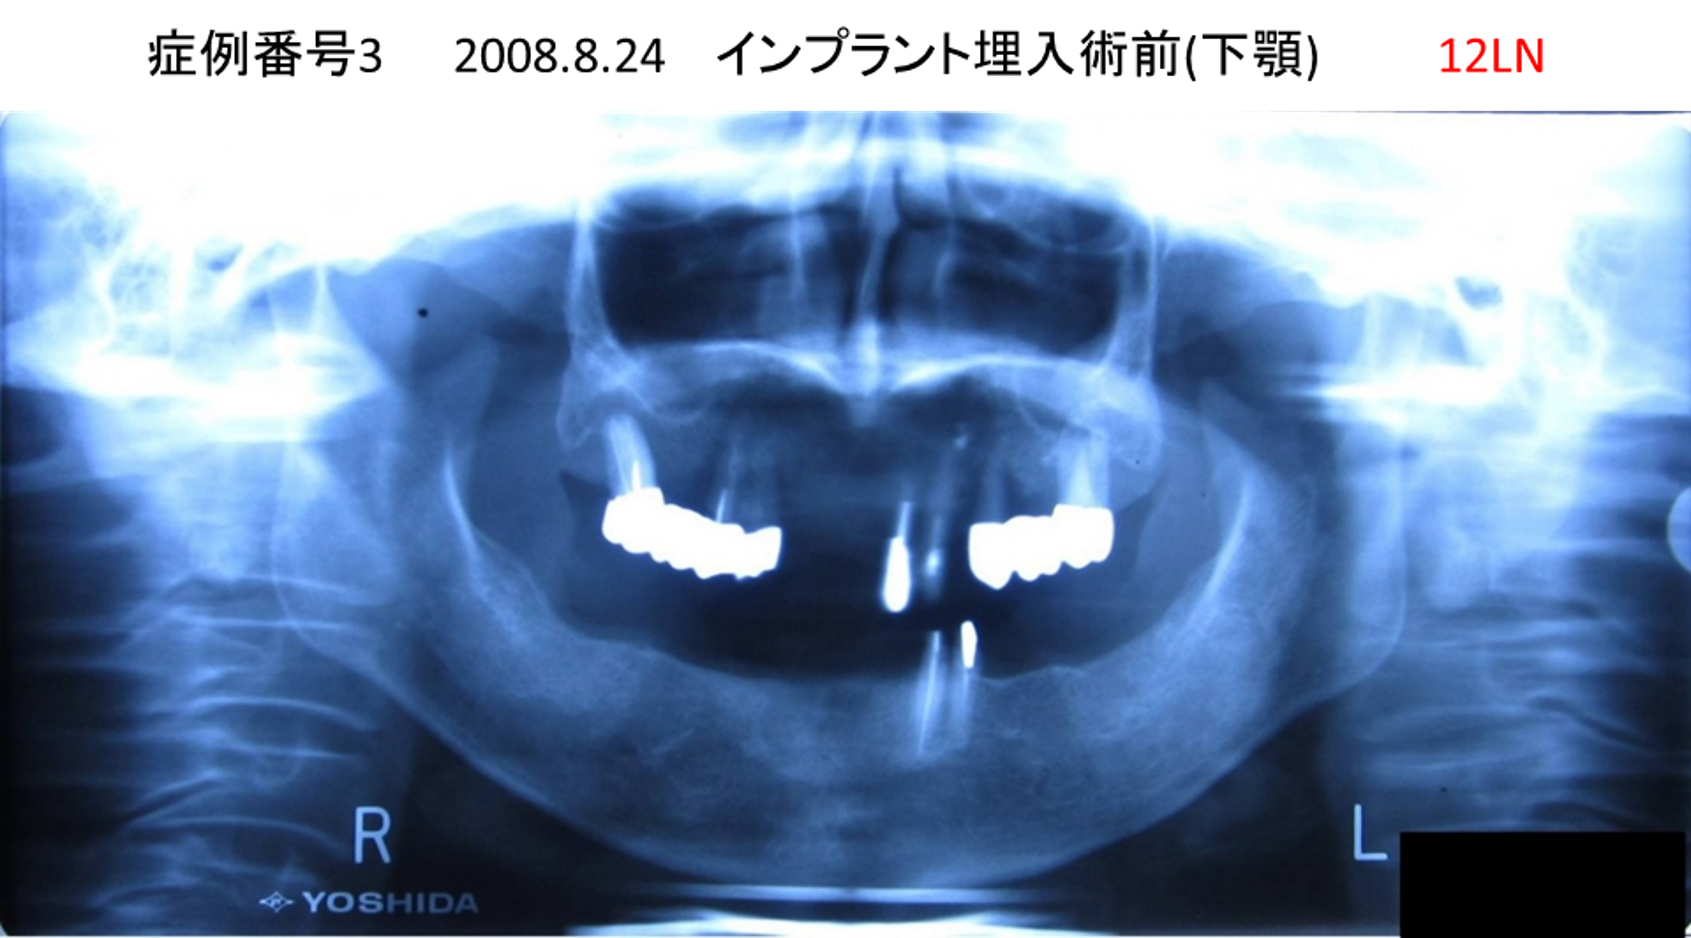

左下の奥歯が痛い患者様のインプラント症例

| 治療名称 |

インプラント |

| 治療費用 |

215万円+税 |

| 治療期間 |

5か月 |

| 患者さんの症状(主訴) |

左下の奥歯が痛い。 |

| 治療内容 |

| 治療結果 |

痛み無く、噛める。 |

| 治療の注意点(リスク/副作用) |

インプラントが壊れたら再治療が必要 |